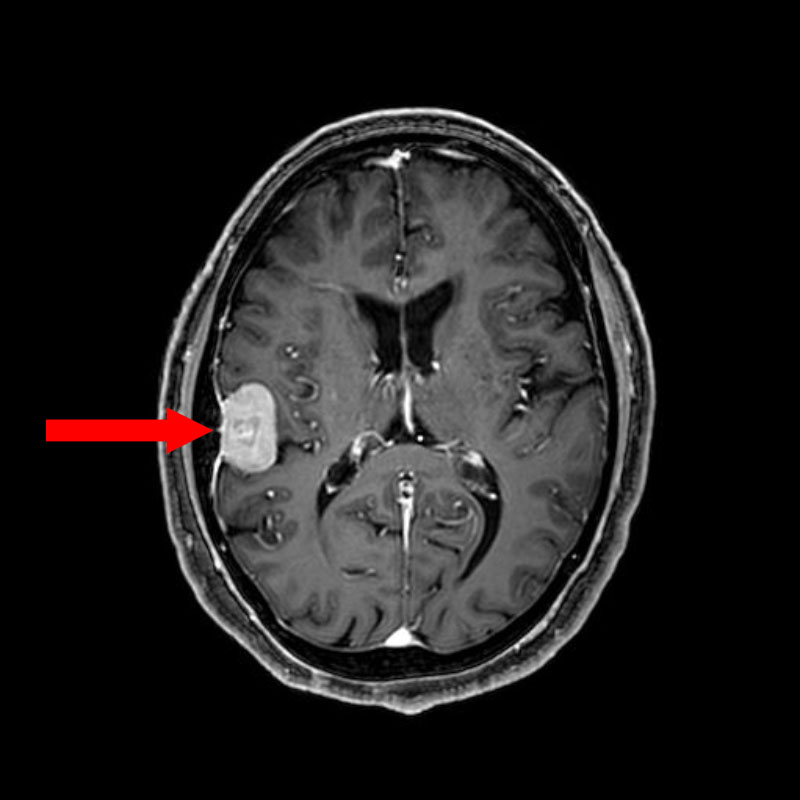

No.’25_81 手術前1

No.’25_81 手術前2